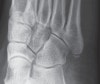

X-ray : 제5중족골 골절(Jones fracture)

Left image : The fracture line passes transversely across the bone.

Right image : A normal unfused 5th metatarsal base apophysis is aligned more longitudinally along the bone.

Developing apophysis는 시상면 방향으로 된 성장판을 가지는데, 골화 중심이 종축 방향이기 때문